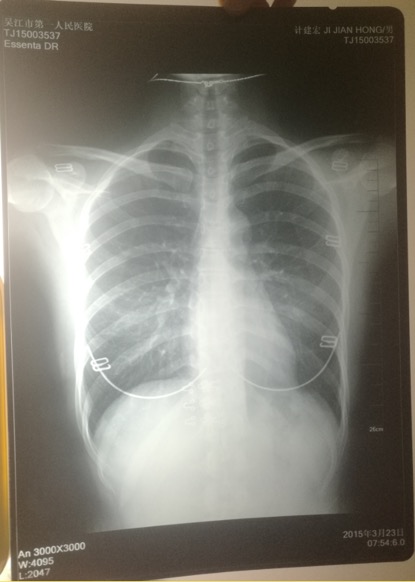

ݐ@2015e323Iqb͕o[Ò˥|YypҳܐޣI̮ڨYĒnLlRڱ`

ݐ2015e3@YypҳܡLlRڱ` k